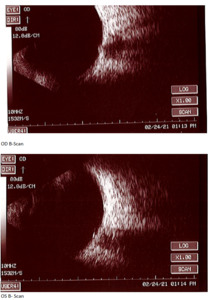

At the end of this visit, a diagnosis of optic nerve head drusen was determined due to the findings on the B-Scan. A highly reflective foci was seen due to the calcification present on the optic nerve head. There was no hyperflourescence seen on the fundus autoflourescent photos, but the drusen were likely buried. A 3-month follow-up was scheduled for repeat dilated fundus exam to ensure hemorrhages were resolving and no changes to the optic nerve head or visual acuity were occurring. The patient was educated on the condition of optic nerve head drusen and its effects on visual fields and vision. He was educated to return to clinic immediately if any changes were noted before the follow-up in 3 months.

B-Scan will show the calcification as a highly reflective foci over the optic nerve using low gain. B-scan imaging has been found a superior test over FAF and computed tomography (CT) to differentiate ONHD and disc edema. It is easy to use, inexpensive, and can even be performed on children. Ultrasonography is dependent upon the calcium content of the drusen. Therefore, some studies have shown that less than 50% of cases of disc drusen are found by ultrasound.7 This is similar with CT scans as well. CT will amplify the drusen in its images if the calcification content is great enough, but is not a method of choice to solely determine optic disc drusen due to high cost, radiation exposure to the patient, and furthermore, any slices greater that 1.5 mm can easily miss disc drusen.7 Overall, B-scan is an excellent test to perform quickly in the determination of disc edema versus optic nerve head drusen, but in some cases drusen could be missed so this may not be the sole test in some cases. For years, B-scan has been considered the gold standard for the diagnosis of ODD, but with the addition of EDI-OCT, physicians may find themselves relying more heavily on newer technology. B-scans do not provide us with clear information about the structural integrity of the neural retina as the OCT does.